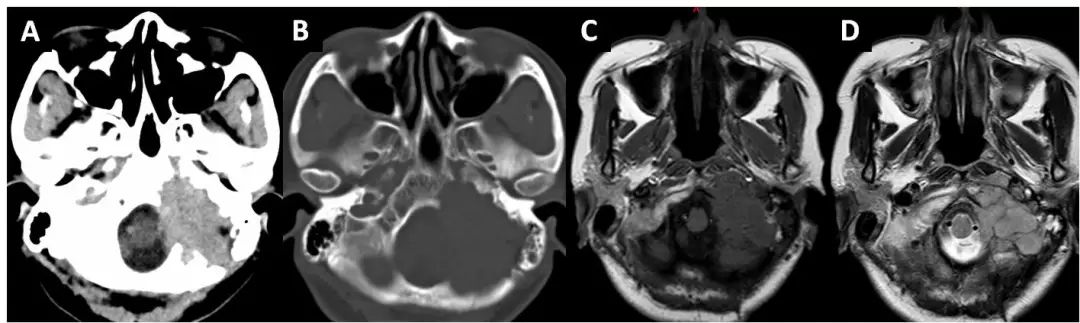

病例一,左侧岩骨,cpa区胆脂瘤.

轴位ct (a)显示左侧岩枕裂中心侵蚀(箭头),伴左侧岩骨ica相邻壁侵蚀.

影像学表现:右侧颞骨岩部骨质破坏,边缘硬化,周围可见软组织肿块,增强

a术前头部ct平扫肿瘤位于左侧岩骨内高密度;b术前岩骨ct见岩骨破坏